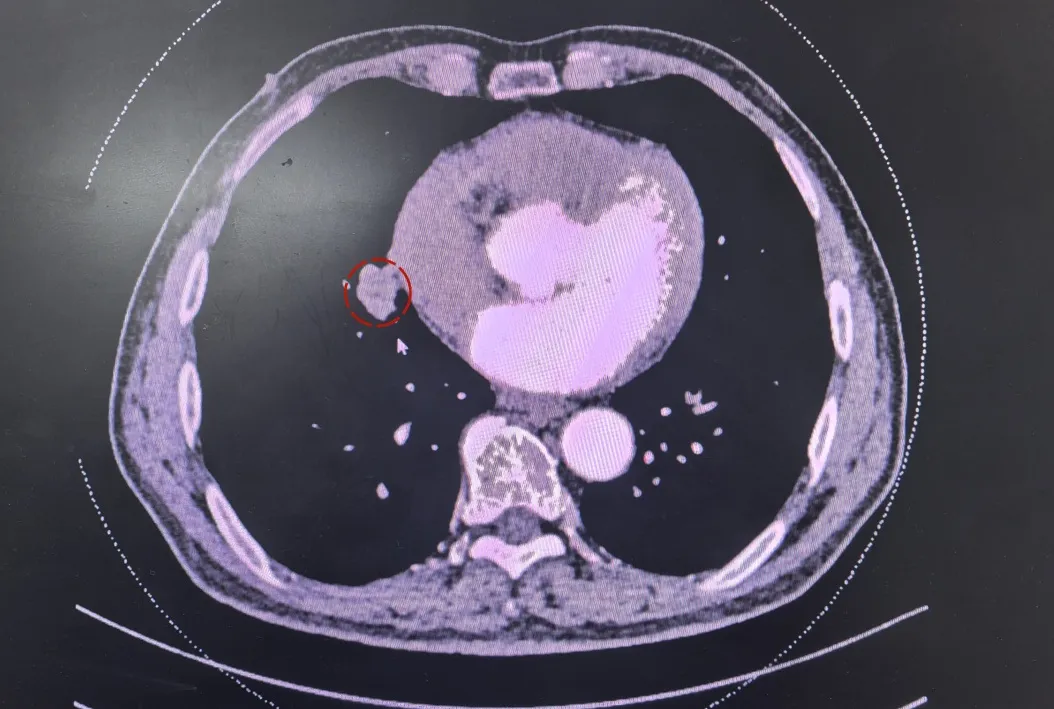

胸外科主任张雪冬接诊并为老人安排住院,完善相关检查,增强CT显示,老人右中肺存在一枚约2.8厘米的实性肿块,靠近肺门。经综合评估,老人的心肺功能及全身状况达标,无手术禁忌,可耐受单孔胸腔镜手术治疗。

在麻醉科的严密监护与支持下,胸外科团队为高老伯实施了单孔胸腔镜右肺中叶肺癌根治术。术中探查证实,病情比术前评估更为复杂:肿瘤已侵犯周围淋巴结并发生气道转移,且与中肺静脉关系密切,给操作带来挑战。张雪冬主任沉着冷静,凭借丰富的临床经验、过硬的心理素质和娴熟的微创技术,精准彻底切除了肺部病灶及区域淋巴结。术后病理报告最终确诊为中分化鳞状细胞癌。